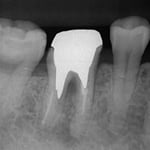

左図を拡大するとよくわかりますが、矢印の部分に確かに破折線がみえます。抜歯宣告を受けて当院を受診された方ですが、これは抜歯にはなりません。

このように、ヒビが見えるだけで、抜歯→インプラントとなるケースが、多くみられるようになってきました。